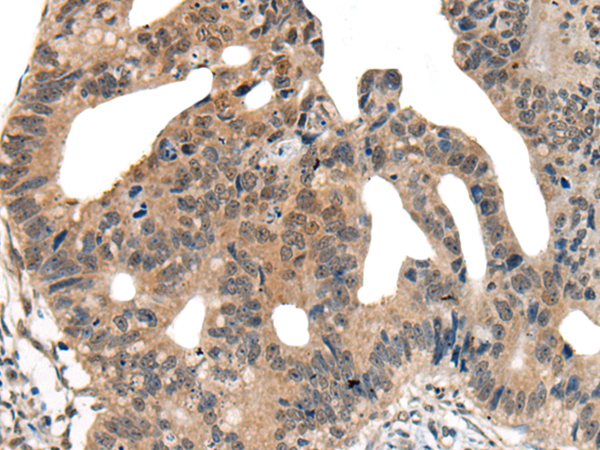

分类: 科研抗体货号: P06279别名:应用: WB,IHC反应种属: Human, Mouse, Rat

分类: 科研抗体货号: P06217别名: NEM7应用: WB,IHC反应种属: Human, Mouse, Rat

分类: 科研抗体货号: P06266别名: NCBP; Sto1; CBP80应用: WB,IHC反应种属: Human, Mouse, Rat

分类: 科研抗体货号: P06210别名:应用: WB,IHC反应种属: Human, Mouse, Rat

分类: 科研抗体货号: P06263别名: CML3; NACED; NAT8-LIKE应用: WB,IHC反应种属: Human, Mouse, Rat

分类: 科研抗体货号: P06205别名: CACC; GOB5; CACC1; CLCRG1; CaCC-1; hCLCA1; hCaCC-1应用: IHC反应种属: Human

分类: 科研抗体货号: P06262别名: DNAS1L2应用: IHC反应种属: Human, Mouse

分类: 科研抗体货号: P06202别名: AMY; CLAC; CLACP; CFEOM5; CLAC-P应用: WB,IHC反应种属: Human, Mouse

分类: 科研抗体货号: P06261别名: DCR2; CD264; TRUNDD; TRAILR4; TRAIL-R4应用: WB,IHC反应种属: Human